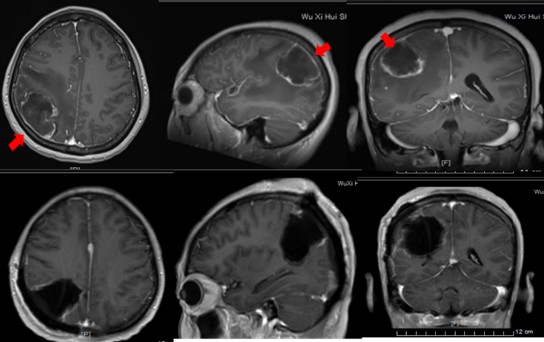

小骨窗微创脑内血肿清除术